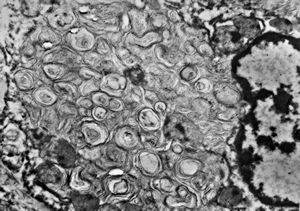

F, 8y. | metachromatic leukodystrophy … n. suralis